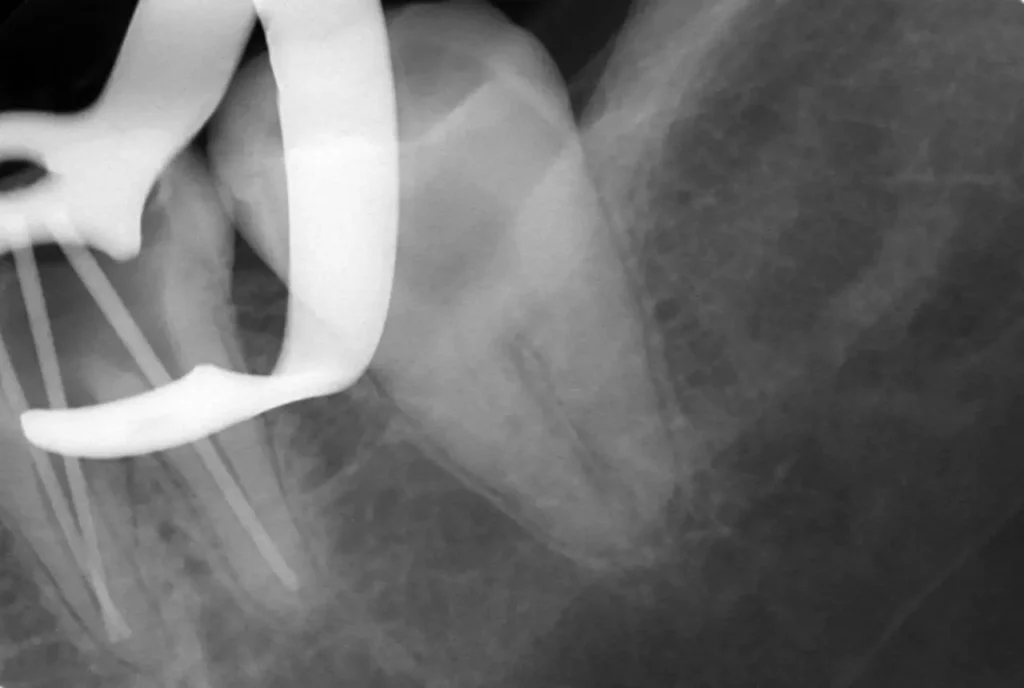

術中(ファイル試適)

レントゲン写真

ラバーダムシートを固定する金具が写っています、シートはバイ菌が

入らないように撮影時にも外しません

術中(ポイント試適)

充填物がきちっとできるように何度も確認します

術後レントゲン写真

見た目よりもいかに無菌的に行えたかが大切です、見た目もきちっとできました